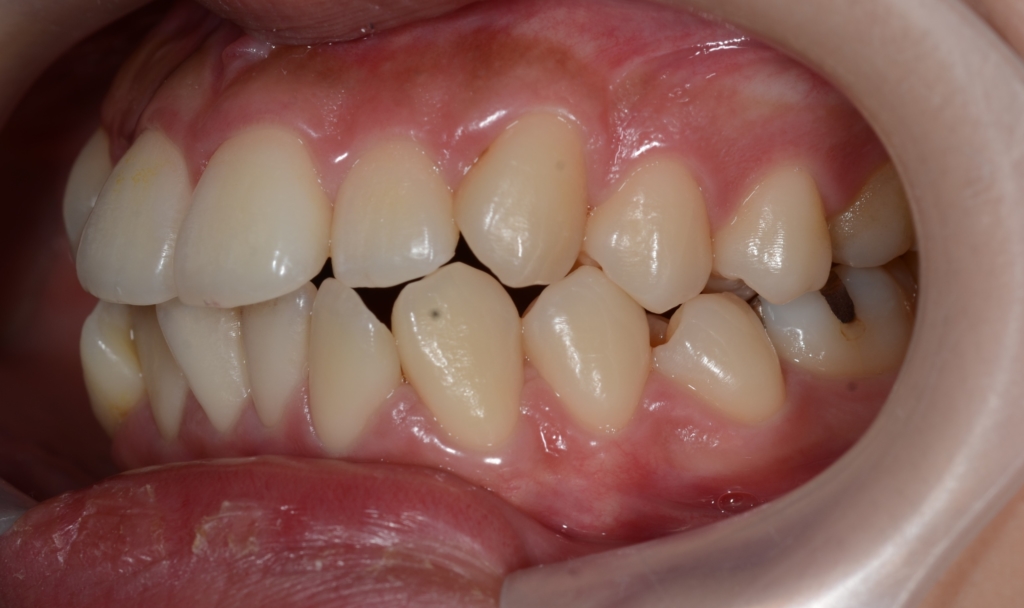

【Before】

しかし、お口を閉じていても、上の前歯がチラリと見えています

この患者さんの場合、

【診断】

#1.上下顎前突

#2.歯と顎の不調和による軽度の叢生

と診断しました。